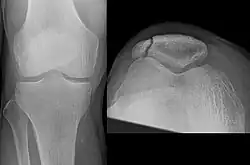

The patella can break in various ways depending on the way it is injured, and into two or more pieces.[1] Types include transverse, the most common, with one fracture line;[5] marginal; osteochondral; and the rare vertical type, or stellate, where a direct compression force gives rise to a comminuted pattern.[5][7] Patella fractures can be further classified as displaced, where the broken ends of bone do not line up correctly and separate by more than 2mm, or undisplaced and stable where pieces of bone remain in contact with each other.[1][7] If fragments of patella bone stick out from the skin it is known as an open patella fracture, and closed if the overlying skin is intact.[1]

Comminuted fracture of patella -

Osteochondral fracture of patella -